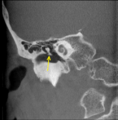

The malleus /ˈmæliəs/ or hammer is a hammer-shaped small bone or ossicle of the middle ear which connects with the incus and is attached to the inner surface of the eardrum. The word is Latin for hammer or mallet. It transmits the sound vibrations from the eardrum to the incus.

The malleus is a bone situated in the middle ear. It is the first of the three ossicles, and attached to the tympanic membrane. The head of the malleus is the large protruding section, which attaches to the incus. The head connects to the neck of malleus, and the bone continues as the handle of malleus, which connects to the tympanic membrane. Between the neck and handle of the malleus, lateral and anterior processes emerge from the bone.[2]

The malleus is one of three ossicles in the middle ear which transmit sound from the tympanic membrane (ear drum) to the inner ear. The malleus receives vibrations from the tympanic membrane and transmits this to the incus.[2]